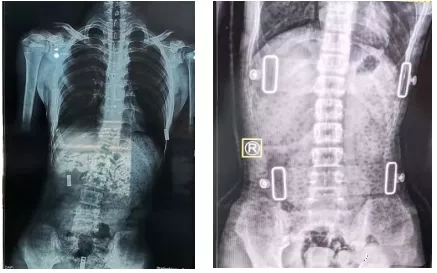

有時戴了支具后脊柱會反方向傾斜。其實,這是因為一般支具治療會采取一種“過度矯正”的方式,以保證脫下支具后身體的反彈更接近于中心線,而不是向原側(cè)彎方向加重。